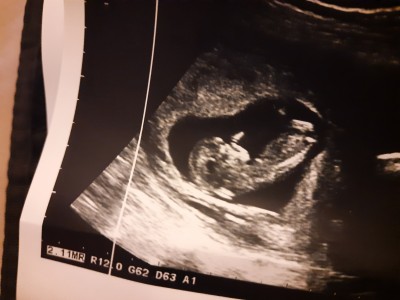

12.haftam doktor erken olduğunu söylüyor ama net değil mi tahminimiz var mı kızlar?

image

erkek kesinlikleee

Bana da öyle geliyor tüm belirtilerimi düşününce. Sağlıklı olsun hiç önemi yok aslında ama insan merak ediyor işte:)